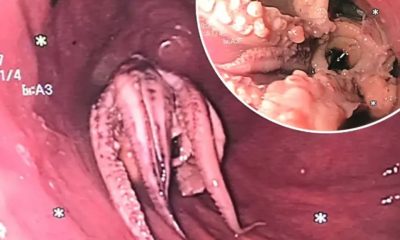

Instituto Jam Press/AGA A descoberta veio após o paciente começar a vomitar sem parar depois de uma refeição que incluía o animal no prato A equipe...